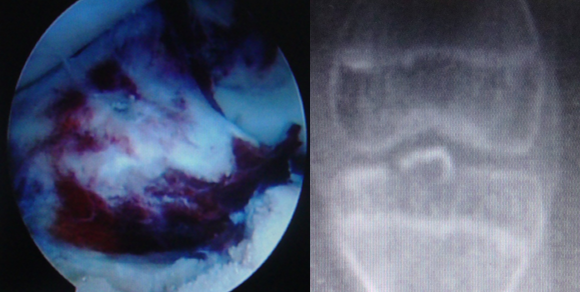

2.带线锚钉治疗肱骨外上髁炎

肱骨外上髁炎:又称网球肘,是肱骨外上髁部伸肌总腱处的慢性损伤性肌筋膜炎,肱骨外上髁炎可由慢性损伤伸肌总腱或退行性变引起或神经源性疾病所致。

肱骨外上髁炎通常采取保守治疗即可取得较好的治疗效果,手术治疗不常用 (报道仅4-8% 的病例用手术治疗),手术治疗分为开放或镜下手术,主要有总伸肌腱肌皮微血管神经束切除术;环状韧带部分切除术;桡侧腕短伸肌延长术;肱骨外上髁的伸肌总腱切断剥离术,重连接止点等。

手术适应症:反复发作、多次治疗无效的肱骨外上髁炎可选择手术治疗。

锚钉选择:GII或Fastin。

带线锚钉术式:先松解桡侧腕短伸肌的止点,然后用两枚锚钉重新连接到肱骨外上髁上。